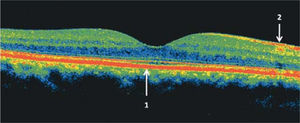

Tomografía de coherencia óptica (OCT) del área macular de un ojo normal. Las zonas más reflectantes tienen colores más cálidos (rojo). En el centro se observa la depresión foveal 1: epitelio pigmentario de la retina, 2: capa de fibras ópticas. En el sector nasal, en dirección a la papila, la capa de fibras ópticas es más gruesa.

El envejecimiento normal afecta especialmente la mono capa del epitelio pigmentario de la retina y la membrana de Bruch que está firmemente unida a la base del epitelio pigmentario (Figura 1). Bajo la membrana de Bruch, está la coriocapilar, fina capa de capilares que nutre a los fotoreceptores (conos y bastones) ya que la fóvea es avascular (requisito para una máxima transparencia). Los nutrientes, provenientes de la coriocapilar, deben ser transportados de la coriocapilar a través de la membrana de Bruch y el epitelio pigmentario.

El epitelio pigmentario retinal tiene un rol esencial en la sobrevida de los fotoreceptores. Los bastones desprenden los discos usados gastados al alba y los conos lo hacen al atardecer. Estos discos son fagocitados por el epitelio pigmentario, que está en íntimo contacto con los segmentos externos de los fotoreceptores (Figura 1). Estos discos gestados son digeridos por la acción de enzimas y degradados para ser reciclados. Sin embargo, con el paso de los años, este mecanismo tan perfecto de renovación circadiana empieza a fallar. Moléculas alteradas por el daño oxidativo no son reconocidas por los enzimas y el material no digerido empieza a acumularse dentro del EP. Estos productos de degradación incompleta constituyen los gránulos de lipofuccina, que se acumulan dentro del epitelio pigmentario.